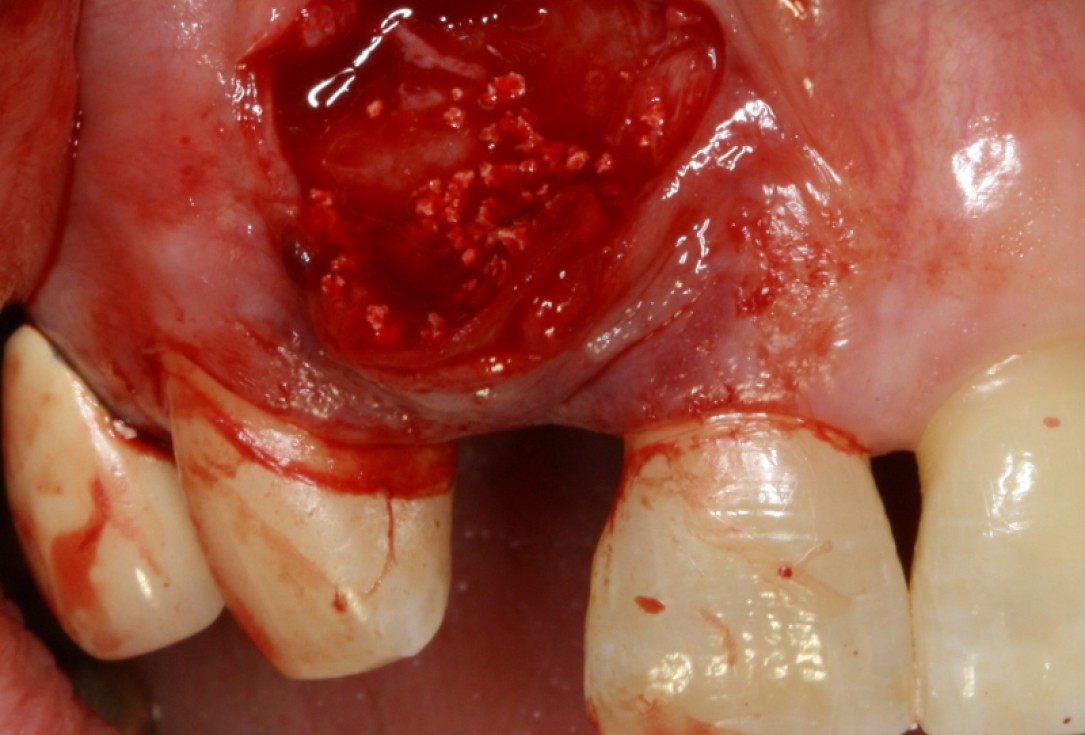

08/20 - Surgical presentation of the alveolar ridgeGBR with maxresorb® & Jason® membrane - Prof. Dr. Dr. D. Rothamel